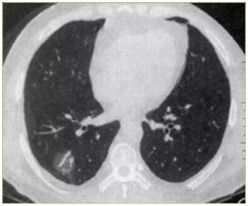

肺部小結(jié)節(jié)通常是指影像檢查(X線或者CT)中發(fā)現(xiàn)的直徑≤2cm的類圓形病灶,≤3cm的稱為結(jié)節(jié),>3cm的稱為腫塊。

也有學(xué)者認(rèn)為,分得太細(xì)并無(wú)意義,例如2.2cm的結(jié)節(jié)與1.9cm的小結(jié)節(jié),臨床上并沒(méi)有本質(zhì)的區(qū)別。在這里我們統(tǒng)一把≤3cm的結(jié)節(jié)統(tǒng)稱為肺部小結(jié)節(jié),在肺部小結(jié)節(jié)中,60%—70%為良性結(jié)節(jié),30%—40%的結(jié)節(jié)方為惡性結(jié)節(jié),所以,發(fā)現(xiàn)肺部小結(jié)節(jié)切勿驚慌。

我們常看到的影像學(xué)描述中的“磨玻璃結(jié)節(jié)(GGO)”,其中一部分是非典型腺瘤樣增生(AAH)或原位腺癌(AIS),結(jié)節(jié)內(nèi)部的實(shí)變與生長(zhǎng)速度的加快(范圍變大)常意味病變性質(zhì)的轉(zhuǎn)變,可以逐步演變?yōu)槲⒔?rùn)腺癌(MIS)、浸潤(rùn)性腺癌(IAC)。